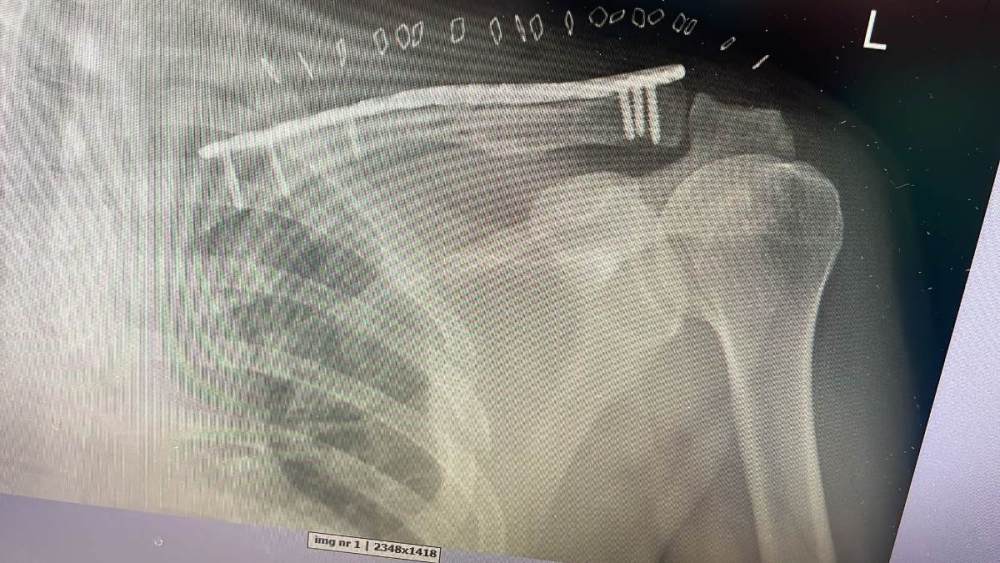

Wydaje mi się, że moje złamanie jest podobne. Na SOR  lekarz powiedział, że samo się zrośnie, ale po konsultacji z innym lekarzem, padła decyzja o operacji. Teraz jest tak. Zastanawia mnie jedynie , dlaczego pomimo skręcenia wpakowali mnie w gips.  Ale nie kłócę się z lekarzem.

Na zdjęciu przed i po operacji.